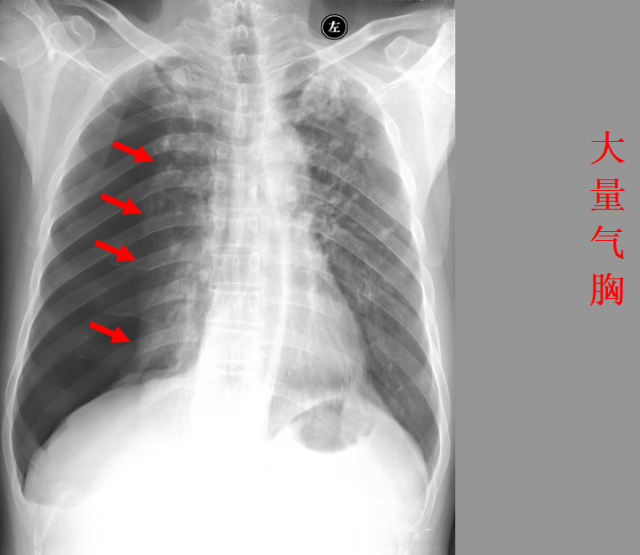

急胸症篇

急腹症篇